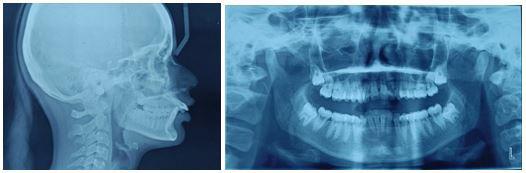

Patient selection: The subjects were patients undergoing active orthodontic treatment from the Orthodontic Specialist Clinic, Kulliyyah of Dentistry, IIUM. Clinical examination and reviews of the patients’ radiological and clinical records were part of the evaluation of the eligible subjects. A mix of study models, cephalometric tracings with the Eastman and Wits Cephalometric analyses performed, and photographs were used to interpret the clinical records.

Cephalometric analysis

Identified subjects underwent comprehensive clinical examination by one of the researchers at IIUM Specialist Clinic to ensure no anomalies in tooth number, morphology and eruption. A lateral cephalometric radiograph was taken as a record for cephalometric analysis. Eastman analysis,12 measuring sellanasion-A-point angle (SNA), sella-nasion-B point angle (SNB), A point-nasion-B point (ANB) and the Wits appraisal (AoBo) were executed.13 The points as illustrates in Figure 1.

SNA angle was used to assess the position of maxilla to cranial base whilst SNB angle was used to determine the position of mandible to the cranial base. The ANB angle, which has been recognized as the most commonly used antero-posterior skeletal

Figure 1: Reference points on the cephalometric radiograph: Sella (S)midpoint of the sella turcica, Nasion (N), A point (A)- deepest point of concavity on the anterior profile of the maxilla, B point (B)- deepest point of concavity on the anterior surface of the mandibular symphysis, Gonion (Go)- the most posterior, inferior point on the angle of the mandible, Menton (Me)- the most inferior point on the mandibular symphysis, Pogonion (Pog)- the most anterior point of the mandibular symphysis, Porion (Po)- the upper midpoint of the external auditory meatus, Anterior nasal spine (ANS), Posterior Nasal Spine (PNS). (Figure reprinted with permission from Siva Dharma D, Abu Bakar N, Mustafa BE. Evaluation of Salivary Leptin Levels and Its Correlation with Class I, Class II, and Class III Facial Skeletal Pattern: A Prefatory Study. European Journal of Dentistry. Published online August 24, 2021. doi:https://doi. org/10.1055/s-0041-1727552)

discrepancy indicator14 was then calculated. It compares the relationship of the maxilla and the mandible with regards to the cranial base. The classification used denotes that a 2-4 degree value indicates a class I malocclusion, above 4 degrees indicates a Class II malocclusion and below 2 degrees is indication for a Class III malocclusion.15

The Wits appraisal, which compares the relationship of the maxilla and the mandible with regards to the functional occlusal plane was used to further confirm the antero-posterior occlusal disharmony. A line is drawn between the cusp tips of the molars and premolars and this is known as the functional occlusal plane (FOP). A perpendicular line is drawn from point A and point B to the FOP to give points AO and BO. The distance between AO and BO is measured. The average (Class I malocclusion) values are −1 mm (± 1.9 mm) for males and 0 mm (± 1.77 mm) for females.15

Values below the average values denote a Class II malocclusion and values above the average denote a Class III malocclusion.

Subjects were grouped into facial classes based on the analysis criteria below:

Cephalometric analysis criteria for Class I facial skeletal pattern:

1. Cephalometric value indicative of Class I based on Eastman (ANB within 2°to 4°, SNA within range of 81°±3° and SNB within range of 78°±3°) as shown in Figure 2.

2. Wits appraisal (AoBo) within Class I (- 2mm to +2mm)

3. Straight facial profile

tracing (right) of a Class I lateral cephalometric radiograph (left). To calculate angles SNA and SNB, lines are drawn between the points S, N, and A. The ANB angle is obtained by deducting angle of SNB from SNA. (Figure reprinted with permission from Siva Dharma D, Abu Bakar N, Mustafa BE. Evaluation of Salivary Leptin Levels and Its Correlation with Class I, Class II, and Class III Facial Skeletal Pattern: A Prefatory Study. European Journal of Dentistry. Published online August 24, 2021. doi:https://doi.org/10.1055/s-0041-1727552)

Cephalometric analysis criteria for Class II facial skeletal pattern:

• Cephalometric analysis with value indicative of Class II based on Eastman analysis (ANB should be >4° and SNB should be <78°) as shown in Figure 3.

• SNA within normal range indicative of average maxilla (81°±3°)

• Positive Wits appraisal (AoBo > 2 mm)

• Convex facial profile

Figure 3: Cephalometric tracing (right) of a Class II lateral cephalometric radiograph (left). To calculate angles SNA and SNB, lines are drawn between the points S, N, and A. The ANB angle is obtained by deducting angle of SNB from SNA. (Figure reprinted with permission from Siva Dharma D, Abu Bakar N, Mustafa BE. Evaluation of Salivary Leptin Levels and Its Correlation with Class I, Class II, and Class III Facial Skeletal Pattern: A Prefatory Study. European Journal of Dentistry. Published online August 24, 2021. doi:https://doi.org/10.1055/s-0041-1727552)

Cephalometric analysis criteria for Class III facial skeletal pattern:

• Cephalometric analysis with value indicative of Class III based on Eastman analysis (ANB should be <2° and SNB should be >81°) as shown in Figure 4.

• Negative Wits appraisal (AoBo) of < - 2mm

• Concave facial profile

Figure 4: Cephalometric tracing (right) of a Class III lateral cephalometric radiograph (left). To calculate angles SNA and SNB, lines are drawn between the points S, N, and A. The ANB angle is obtained by deducting angle of SNB from SNA. (Figure reprinted with permission from Siva Dharma D, Abu Bakar N, Mustafa BE. Evaluation of Salivary Leptin Levels and Its Correlation with Class I, Class II, and Class III Facial Skeletal Pattern: A Prefatory Study. European Journal of Dentistry. Published online August 24, 2021. doi:https://doi.org/10.1055/s-0041-1727552)